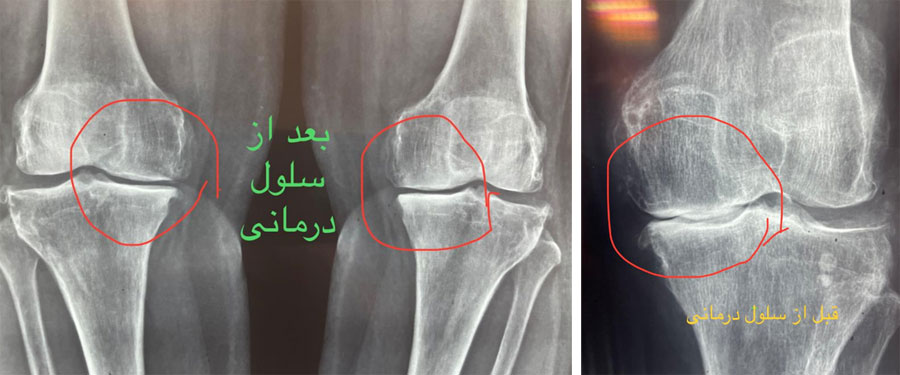

تکنولوژیهای درمانی نوینی مانند سلولدرمانی با بهرهگیری از سلولهای بنیادی، چشماندازهای جدیدی برای بازسازی آسیبهای مفصل زانو به وجود آوردهاند.

در این روش، سلولهای بنیادی، که از منابعی چون مغز استخوان یا بافت چربی بیمار استخراج شدهاند، جدا و تکثیر میشوند. سپس این سلولها به داخل مفصل زانو تزریق میشوند.

این سلولهای بنیادی دارای توانایی ترمیم بافتهای آسیبدیده مفصل، از جمله غضروف، رباط و منیسک هستند. علاوه بر این، آنها به کاهش التهاب، احیای سلولهای مفصلی، و در نهایت بهبود عملکرد مفصل منجر میشوند.

مطالعات نشان دادهاند که سلولدرمانی میتواند به بهبود درد مفصل، افزایش دامنه حرکتی، و بهبود کیفیت زندگی بیماران مبتلا به آرتریت و آسیبهای مفصل زانو کمک موثری نماید.

ولی جدیدترین روشی که امروزه در تمام دنیا برای درمان ارتروز و ساییدگی زانو و ستون فقرات استفاده میشود تزریق مستقیم سلولهای بنیادی داخل زانو یا ستون فقرات یا همان سلول درمانی است . مزیت سلول درمانی نسبت به روشهای پیشین از جمله تزریق ازن یا پی آر پی اینست که این روشها بیشتر برای مفصل حالت تسکین ایجاد میکنند و در واقع مسکن هستند در حالیکه سلول درمانی منجر به تشکیل غضروف در مفصل شده و از طریق ایجاد غضروف درد را از بین میبرد .